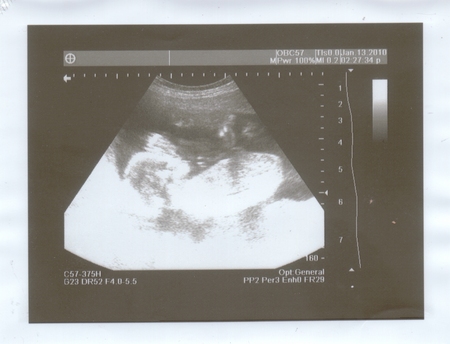

Моё УЗИ 18 недель и 5 дней. Скрининг (II).

Ну значит, все по порядку! Пришла на УЗИ, врач помазала живот и давай в экран смотреть. А я на неё! Она в очках.. и там чуть чуть отражает малыша))))) Ну вообщем, говорит, все хорошо, развиваемся по сроку, плацента высоко, вод нормальное количество, малыш сидит попкой к низу. Сказала, что ещё перевернется. Активно очень крутится))) И говорит, ну что? Пол хотите знать???? Я - КОНЕЧНО)))))))) Она - Мальчик!))))) Я - Это точно???? Она - если бы не была так уверена, не сказала бы! Я в шоке)))) Я, конечно, рада, ведь не пол главное))) Но как-то внутренне.. ожидала девочку. Зато МУЖ так СЧАСТЛИВ!!!!! Ради таких моментов я готова на все ,чтобы видеть счастье любимого человека))) Потом врач повернула мне монитор, и я увидела своего сынулю!!! Даже не верится - СЫНУЛЯ)))) У меня будет сын)))))) Он так крутился, ротик открывал - закрывал) Так мило!!!! Я попросила фото, она говорит, что будет плохого качества, а мне всеравно, на память-то!!! ))) Так что смотрите:

Видно на фотке, как малыш возле головы ручку поднял, и ножки к верху задрал))) Вот так.

Следующее УЗИ должно быть на 23-24 неделе теперь)